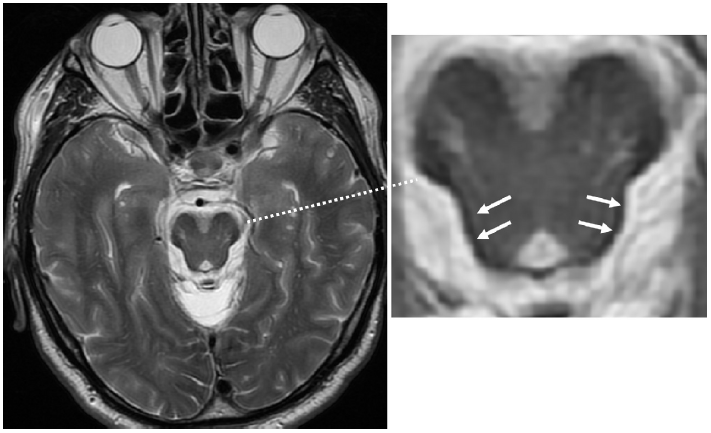

当存在糖尿病

或高血压

等心血管危险因素时,血管原因可能是急性小脑综合征的主要原因(图 1),并且血管病变可导致小脑实质部分萎缩(图 2)。

图 1 患有多种心血管危险因素的患者出现后颅窝多发性卒中。左:头颅MRI T2加权序列图像可见脑干和小脑实质存在高信号病灶(箭头)。中右:头颅MRI T1加权序列图像可见低信号病灶(箭头)。